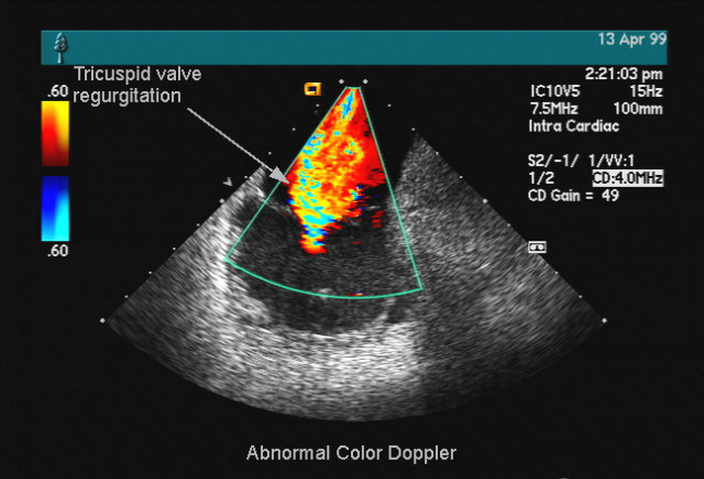

彩色多普勒血流成像的意义

即从彩色多普勒血流成像中,可观察了解血流的有关特点及其意义

1.显示出二维超声成像中未能检出的血流比较小的动、静脉血管,用二维超声常常不能显示其血管壁,非心血管系的其他系统、器官,尽管位置比较表浅,也常见这种情况。例如颅内血管,目前只有大脑中动脉的片断在部分患者中可显示其血管壁。用彩色多普勒血流成像,可以使3mm以下的小血管的血流成像,因此可以检出实质脏器肿瘤如肝、肾等肿瘤的血流。

朝向探头的血流以红色信号表示,背向探头的血流为蓝色信号,例如在心尖四腔图,从左房到左室有一股红色的血流信号,结合心血管的解剖生理知识,以及不同彩色标志血流的方向,可以判断血流起源于左房。右主动脉窦瘤破裂向右室时,在收缩期、舒张期均有分流血流信号,室间隔缺损以左向右分流为主时,收缩期分流血流明显,只要观察到分流血流,可以判断是收缩期的血流。

5.反映血流的性质

正常层流的彩色多普勒血流成像,彩色的血流信号显示色彩比较均匀,用较低的速度标尺时,血管腔******部分彩色的亮度高于外缘近血管壁处,如用较高的速度标尺,则为均匀的彩色,彩色信号的亮度从血管腔******到外缘没有差别。瓣口狭窄、以及心腔内、心腔与大血管间的分流血流,在其最高速的部分即射流(jet f10w),因流速常超过仪器测速度的Nyquist极限,血流的彩色信号常出现彩色混叠。颈总动脉的血流进入颈动脉分叉时,因管腔从大小均一突变为膨大,血流在膨大部的边缘出现血流分离及旋涡流,即血流方向与颈总动脉、颈动脉分叉部******的血流方向相反,用彩色多普勒检测可清晰显示颈动脉分叉处的旋涡流。

6.表达血流速度的快慢

4.彩色信号混叠或倒错

即在同一方向上的血流信号,呈现红、蓝色同时存在,其产生往往与仪器调节不当有关。对高流速的血流,使用了低的速度标尺、低的脉冲重复频率、高的超声频率,容易引起彩色信号混叠,把以上使用条件改变,可以消除彩色信号倒错。如已使用最高的速度标尺、最高的脉冲重复频率和最低频的探头,被检的高速血流仍出现彩色混叠,呈所谓五彩镶嵌,这时的彩色混叠,具有诊断意义,说明被检测的是高速血流。